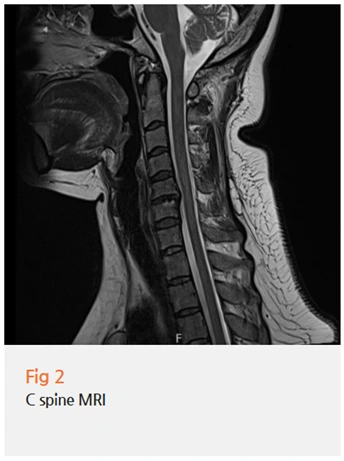

✔️ 목 MRI - 경추에 문제가 있어서 얼굴 쪽으로 연관통이 오는 건 아닌지

검사 결과, 뇌에는 문제가 없었어요.

그런데 목 쪽, 즉 경추부에 구조적인 문제가 확인됐어요.

환자분께 설명드렸어요.

삼차신경통이 아니라 경추 문제로

인한 비정형 안면통증이라고요.